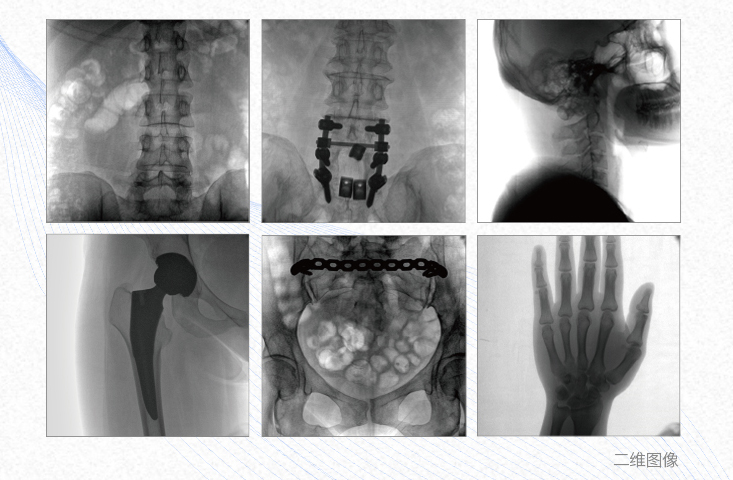

有效重建復雜的脊柱三維模型,提供準確的二維、三維圖像,提高螺釘植入的準確性,縮短手術(shù)時間,減少并發(fā)癥的概率,降低輻射的攝入。

2、創(chuàng)傷外科

例如骨盆骨折內(nèi)固定術(shù),可術(shù)中三維重建髖臼關(guān)節(jié)面,準確定位并植入螺釘,有效縮短螺釘植入的時間和透視暴露時間,減少術(shù)中及術(shù)后并發(fā)癥發(fā)生的概率。

3、關(guān)節(jié)外科

主要應用于肩關(guān)節(jié)、肘關(guān)節(jié)、髖關(guān)節(jié)、膝關(guān)節(jié)的關(guān)節(jié)置換及解剖復位的定位。它可以準確地置入假體,減少輻射時間,降低輻射劑量。

4、截骨矯形外科

例如治療先天性脊柱側(cè)后凸畸形,可有效引導術(shù)者植入后路螺釘并切除半錐體,達到滿意的截骨矯正效果。